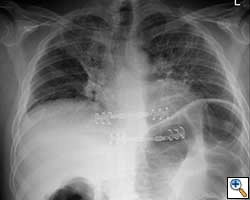

- Chest wall resection for malignancy (Figures 4-5)

![]() |

| Figure 4: Model showing application in chest wall resection. | Figure 5: Postoperative chest x-ray showing the implants |

Here we present, as a paradigm of repair, the case of a 65 year old gentleman referred to our institution for an indolent mass in the left anterior chest wall. Repairs for other conditions follow the same rules. This mass had been stable in size for more than 12 months and the patient was prompted to seek medical attention as, after weight loss due to dieting, he felt the mass was uncomfortable while sleeping. Apart from coronary stenting for angina, the past medical history was unremarkable.

Computed tomography scan of the chest showed a mass protruding from the cortex of the third rib. A percutaneous core biopsy was non-diagnostic. We proceeded to an open incisional biopsy. This was reported as showing a spindle cell neoplasm. The patient was therefore scheduled, after multidisciplinary meeting discussion, for radical surgery.

At surgery, the mass was arising from the cortex of the third rib, and solid measuring 5x8 cm. There was no macroscopic involvement of the surrounding extra-thoracic musculature or of the underlying lung, the mass being confined to the rib and intercostal muscles. The patient underwent resection of the second to fourth ribs and the rhomboid muscle as well, in the attempt to get clear margin. The large antero-lateral defect was eventually reconstructed using 2 mouldable titanium bars. To prevent lung herniation through the defect, we reconstructed the layers anatomically using a biological patch (Veritas®). The final histopathology was a low grade sarcoma of the chest wall with clear resection margins.

He made an excellent recovery with daily physiotherapy to encourage shoulder movements. He was discharged with oral analgesia on postoperative day 4. At 1-month follow-up the patient had no pain at all, discontinued analgesia on postoperative day 17 and demonstrated a full range of shoulder movement. His chest x-ray was unremarkable and the wound healed without complication.